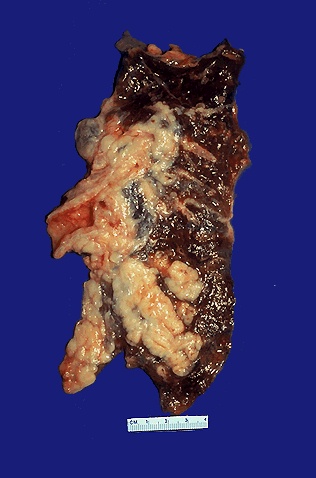

Another form of lung cancer. ((http://www-medlib.med.utah.edu/WebPath/webpath.html#MENU)  |

Liver cancer. (The entire liver should look like the liver in the right half of the photo. ) From http://www.nycenet.edu/csd16/  |